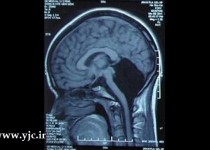

یک خانم چینی پس از 24 سال زندگی متوجه شد که نیمی از مغز او وجود ندارد و جمجعه اش تقریبا نصفه پر شده است. این مشکل بسیار نادر است و سال ها بود که کسی با این وضعیت رویت نشده بود.

پزشکان بیمارستان نظامی در منطقه شاندونگ پس از مراجعه این خانم از او آزمایش هایی گرفتند که در نهایت مشخص شد وی با نیمی از مغزش زندگی می کند. این خانم به خاطر سردردهای دائمی و سرگیجه به بیمارستان مراجعه کرده بود.

اسکن ها نشان می دهد که این خانم تنها با قسمتی از مغزش که مسئولیت حرکات بدن، تعادل و صحبت کردن را دارد به دنیا آمده است. پزشکان در مورد این خانم دچار شک شده اند که چطور او تا به این سن زنده مانده است.

این مشکل باعث شده است که وی تا سن 6 سالگی توانایی صحبت کردن را نداشته و برای اولین بار در 7 سالگی روی پای خودش ایستاده است. به نظر می رسد که این مادر این خانم در دوران بارداری دچار بیماری خاصی شده که این مشکل نتیجه آن بوده است.